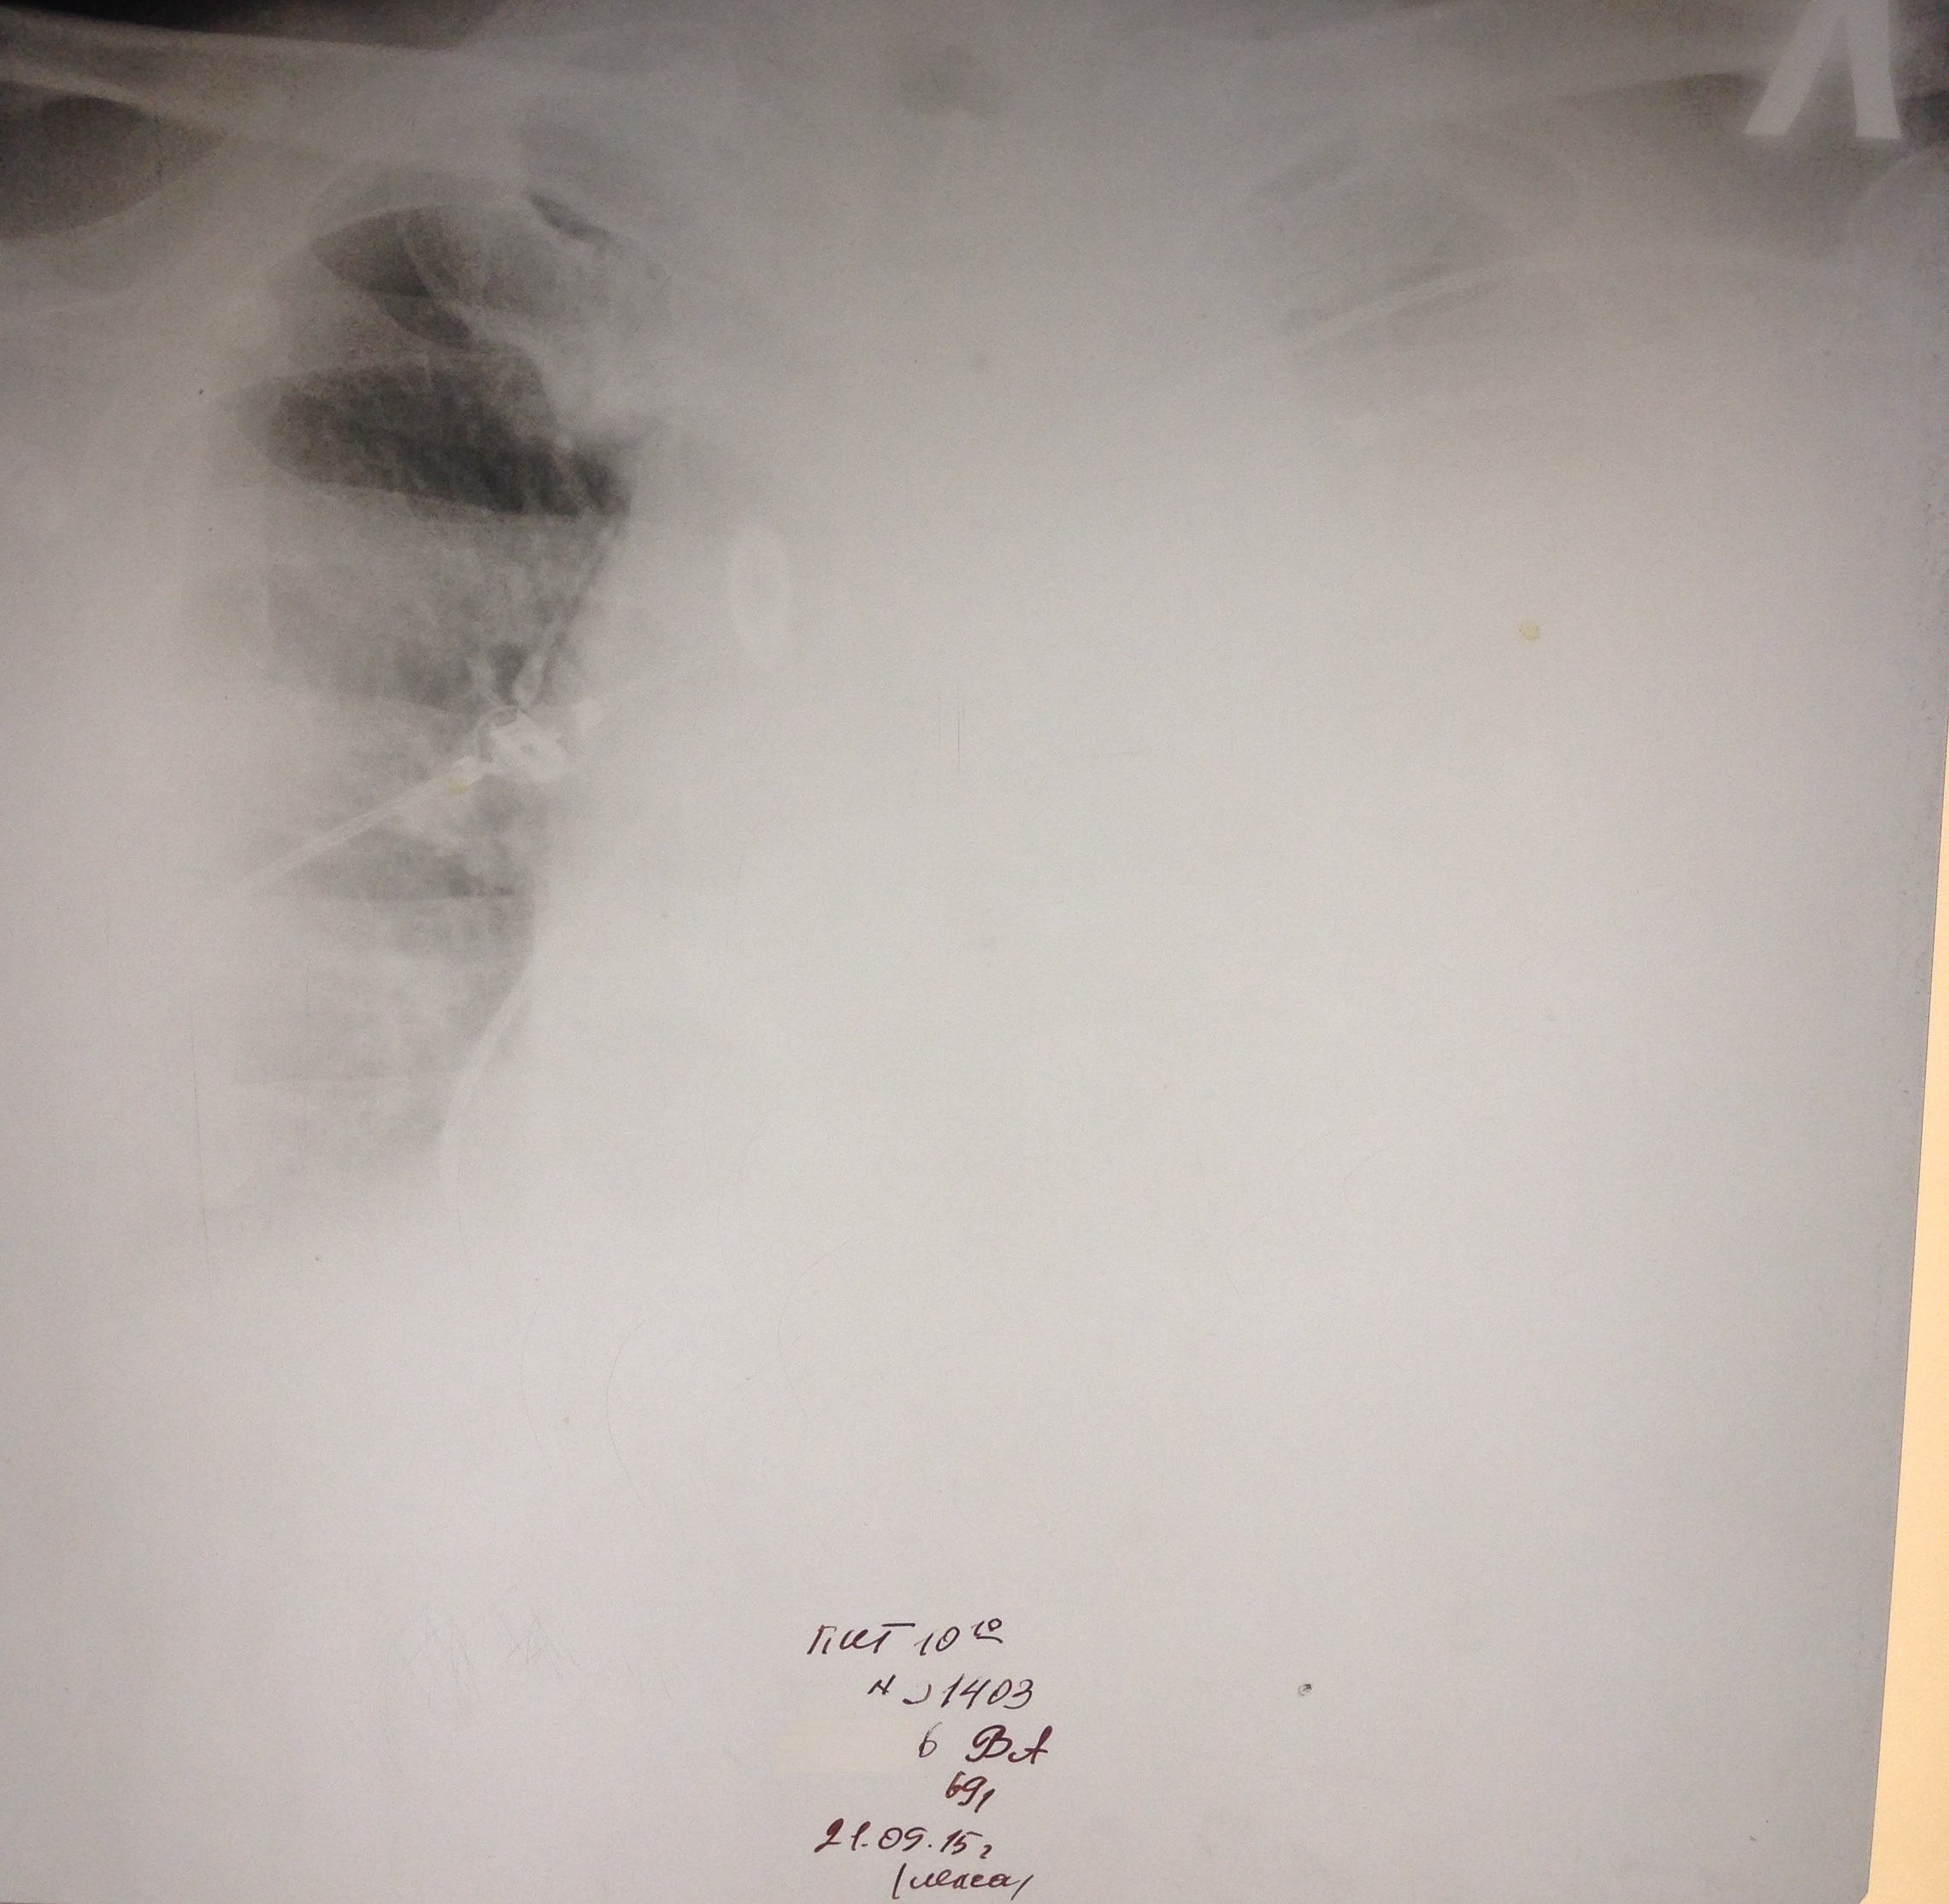

М, 69 лет. РАА. На первом снимке расширение срединной тени. На втором гемоторакс в результате прорыва крови из аорты в плевральную полость.